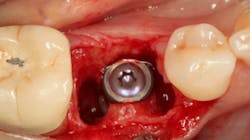

An osteotomy was then created, extending to the apical portion of the split ridge in preparation for implant placement. A bone-level tapered 4.1- x 12-mm implant was placed with a flat cover screw. A mixture of cancellous and cortical allograft particulate was infused with autogenous PRGF and packed around the implant on the mesial and distal aspects. The newly out-fractured buccal plate was positioned intimately adjacent to the buccal portion of the implant, and additional graft material was placed over the buccal plate to further augment the bone horizontally and reduce the risk of buccal-plate resorption during healing. A 25- x 30-mm Ossix Plus membrane was soaked in saline for three minutes and trimmed to extend 3–4 mm beyond the confines of the bone graft and roughly 1 mm from the adjacent teeth.

After the photo was taken to demonstrate the membrane placement, a periosteal elevator was used to further push the membrane under the lingual flap so that it draped intimately over the graft. The partial-thickness flap preparation made during initial incisions allowed for coronal positioning for tension-free primary closure. A CV-5 horizontal mattress suture was used to bring the buccal and lingual flaps together, and closure was completed with interrupted sutures.